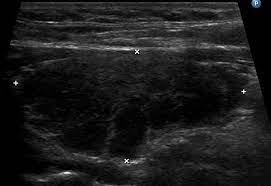

- 초음파 검사: 갑상선 초음파 검사를 통해 갑상선의 크기와 모양, 이상 징후 등을 확인할 수 있습니다.